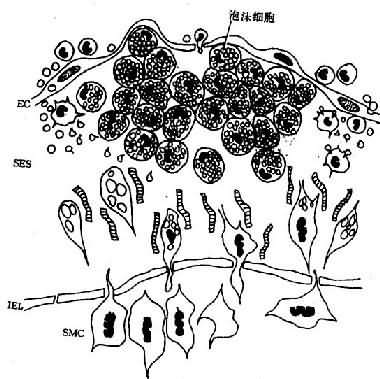

大量泡沫细胞聚集即形成脂纹,内皮隆起及变形。电镜下,巨噬细胞源性泡沫细胞表面富有突起,形成丝状伪足;胞浆内含有大量较小的脂质空泡和溶酶体,有时还见到胆固醇结晶;核卵圆或略呈肾形,异染色质常呈块状紧靠核膜,偶见1~2个核仁。内皮细胞、巨噬细胞及SMC均可分泌生长因子〔PDGF、纤维母细胞生长因子(FGF)、表皮生长因子(EGF)等〕,在其作用下,原已存在于内膜的SMC增生;中膜SMC发生表型转变(phenotypic modulation),即由收缩型(胞浆内含大量肌丝及致密体)转变为合成型(含大量粗面内质网、核蛋白体及线粒体);同时,SMC穿过内弹力板窗孔迁移入内皮下间隙并增生。SMC表面有LDL受体,可结合、摄取LDL及VLDL而成为泡沫细胞(肌源性泡沫细胞)。电镜下,肌源性泡沫细胞多呈长形,或有突起,多少保持SMC的特点,胞浆内可见肌丝和致密体,脂质空泡多少不定,一般稍大,有时能见到基底膜(图8-2)。

图8-2 脂纹组织结构模式图

内皮下间隙(SES)大量巨噬细胞源性泡沫细胞聚集,中膜SMC穿过内弹性膜(IEL)窗孔迁入内膜,增生并摄取脂质,内膜隆起及变形EC:内皮细胞病变的进展:已知OX-LDL具有细胞毒性,当大量OX-LDL被巨噬细胞摄取,超过了其清除能力时可引起泡沫细胞的坏死,导致细胞外脂质核心形成。加之,SMC大量增生,穿插于巨噬细胞源性泡沫细胞之间,产生胶原、弹性纤维及蛋白多糖,使病变演变为纤维斑块(图8-3)。